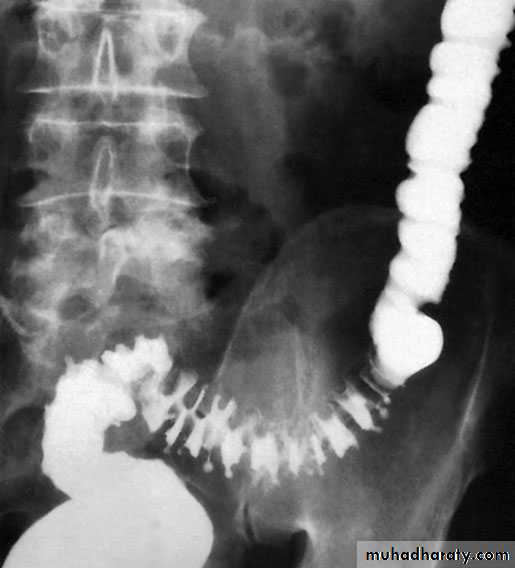

Barium enema showing sigmoid diverticular disease ‘saw-teeth’ and diverticula

Excessive segmentation in response to food, prostigmine and morphine is found in colonic motility studies, and this exaggerated response is more apparent in symp­tomatic than in asymptomatic individuals. On histological inves­tigation, the diverticulum consists of a protrusion of mucous membranes covered with peritoneum. There is thickening of the circular muscle fibres of the intestine, which develops a con-certina or saw-tooth appearance on barium enema .

Water-soluble contrast enemas may, however, be helpful in sorting out patients with large bowel obstruction. Barium radiology is carried out to exclude a carcinoma and to assess the extent of the disease. Where the sigmoid colon is thickened and narrowed, a 'saw-tooth’ appearance may be seen.

Some strictures can be very difficult to distinguish by radiology alone, and in those-circumstances colonos­copy will be necessary to rule out a carcinoma.